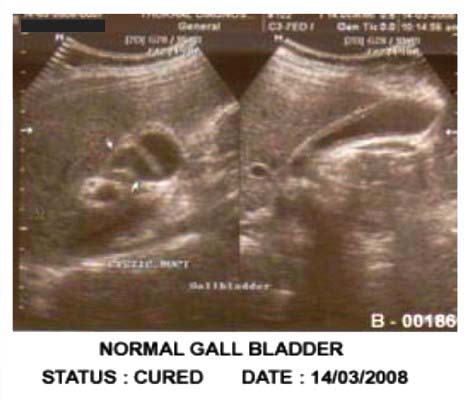

After Treatment:

Patient remained asymptomatic. Patient again sent for Ultrasonography after few days. Ultrasonography Report showed gall bladder is normal in shape and outline. There was no evidence of any calculus in GB lumen.